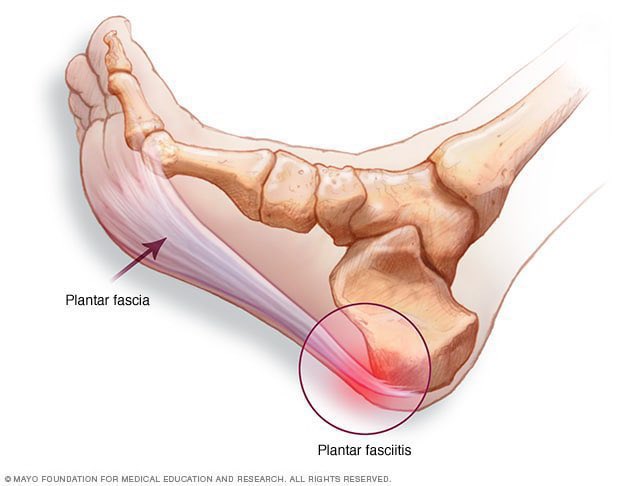

يحدث الالتهاب في الأنسجة التي تمتد عبر الجزء السفلي من القدم (شوف الصورة 👇)

ويربط بين عظم العَقِب "كعب القدم"

و يمتد إلى أصابع القدمين و تسمى هذه

#اللفافة_الأخمصية

يحدث الالتهاب في الأنسجة التي تمتد عبر الجزء السفلي من القدم (شوف الصورة 👇)

ويربط بين عظم العَقِب "كعب القدم"

و يمتد إلى أصابع القدمين و تسمى هذه

#اللفافة_الأخمصية